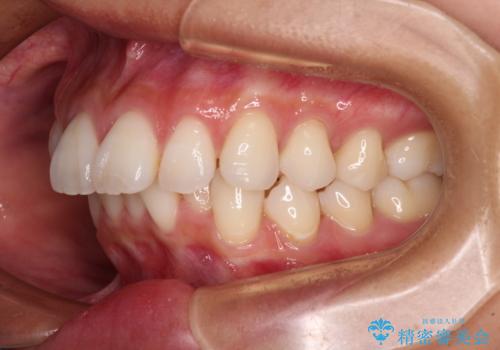

- 飛び出した前歯を気にして来院された患者様です。

口元を引っ込めるために上下左右の第一小臼歯4本を抜歯することとしました。

途中妊娠と出産がありましたが、予定よりも早く治療を終えることができました。